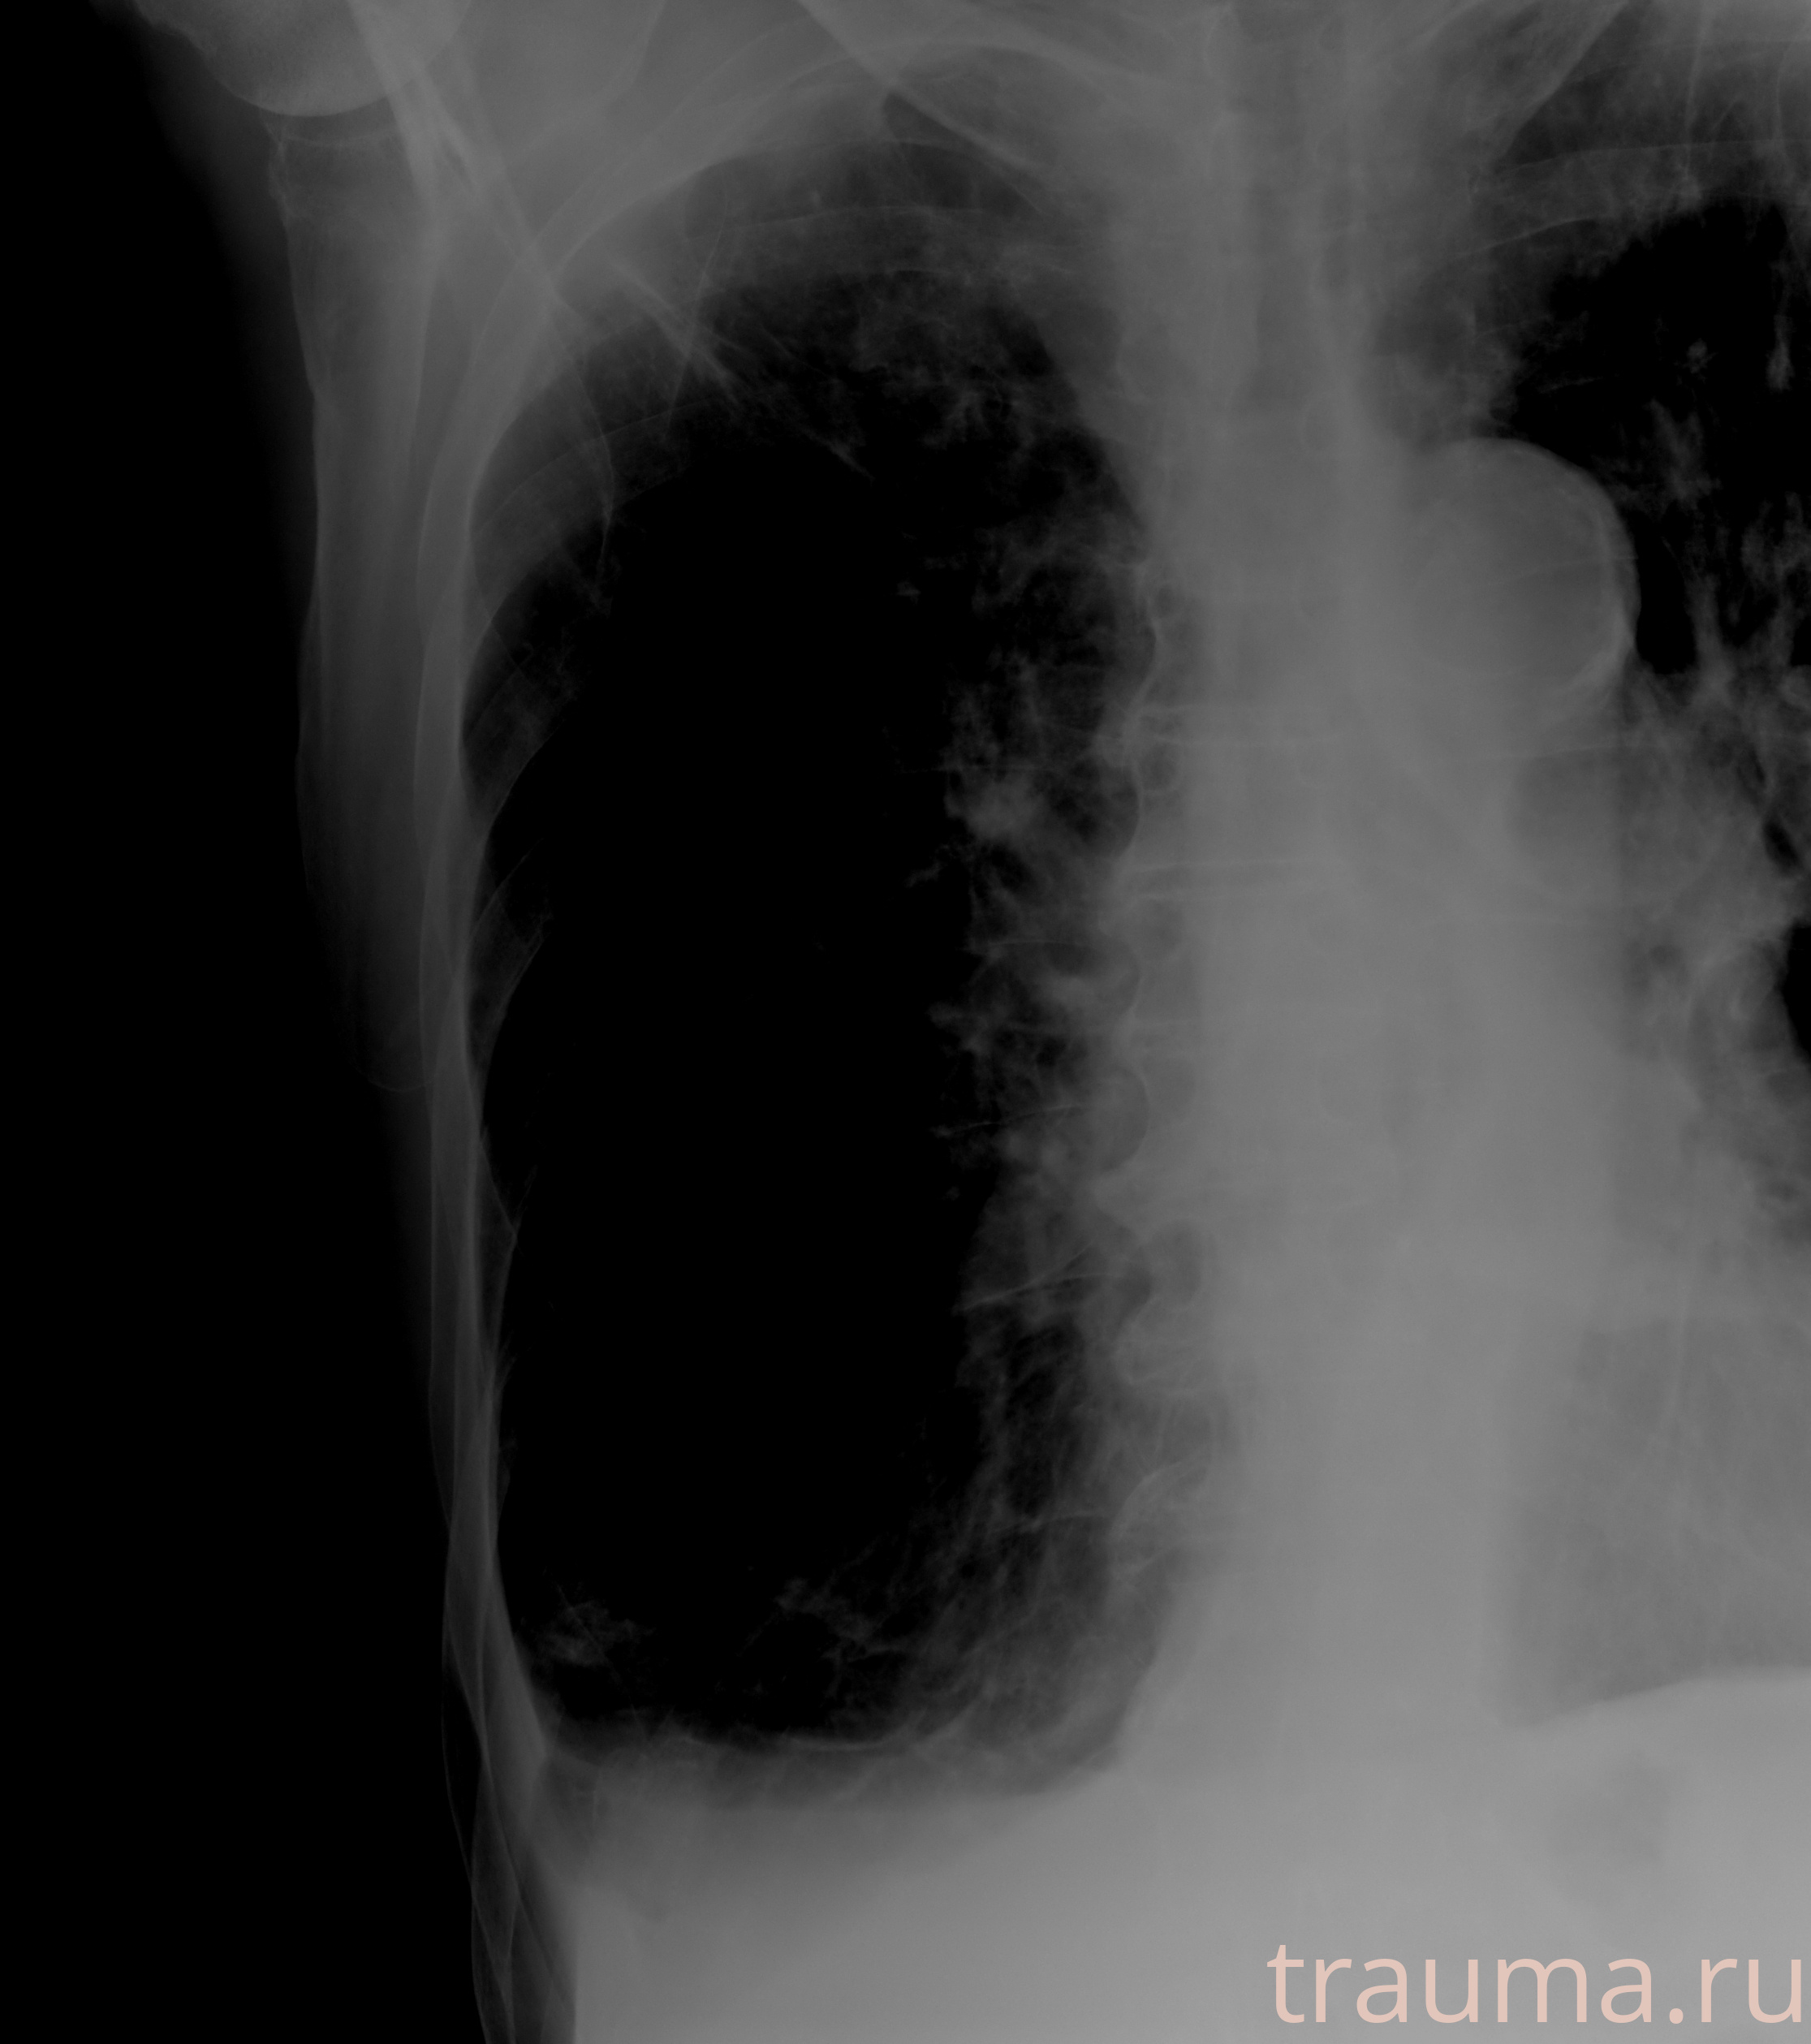

Рентген на дому: по вашему адресу приезжает врач-рентгенолог, травматолог-ортопед с мобильным рентгеновским аппаратом, проводит диагностику травмы или заболевания, делает необходимые рентгенограммы, дает рекомендации по дальнейшему лечению. Получить качественные снимки в домашних условиях возможно благодаря уникальной методике, разработанной МосРентген Центром для института  Склифосовского